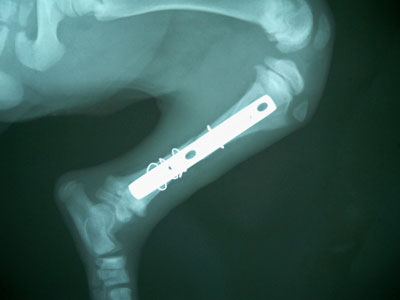

Μετά την ανάταξη του κατάγματος και την συγκράτηση του απολλύματος με μεταλλικό ράμμα τοποθετήθηκε στην έσω επιφάνεια της κνήμης μεταλλική πλάκα 2,7mm και 3 κοχλίες 2,7 mm στο κεντρικό τμήμα και 3 κοχλίες 2,7 mm στο περιφερικό.Κατά την διάρκεια του χειρουργείου διαπιστώθηκε ο,τι κλώτσησαν 4 από τους κοχλίες. 3 περιφερικά και γι΄ αυτό τοποθετήθηκαν δύο μεταλλικά ράμματα και 1 κοχλίας κεντρικά και τοποθετήθηκε 1 μεταλλικό ράμμα.